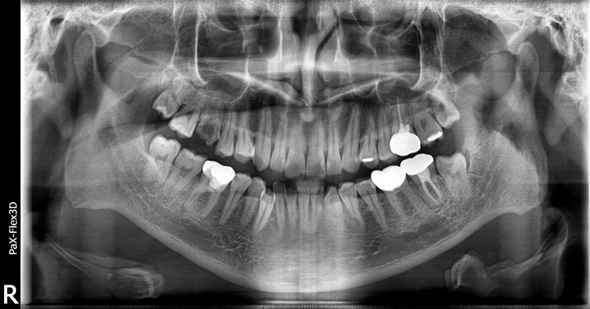

(전) 2022-05-10 (후) 2022-08-25

잇몸뼈의 높이가 충분하지 않아 상악동거상술 및 뼈이식을 진행하고 3개월 후 임플란트를 식립했습니다.

(전) 2022-05-10 (후) 2022-11-14